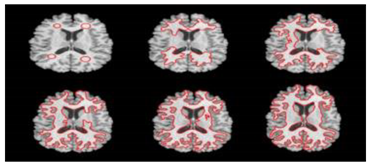

- Fuzzy C-means: FCM [19,53,58,59,60,61,62,63,64] is an unsupervised deterministic method which represents the advanced version of k-means. It is based on the theory of fuzzy subsets giving rise to the concept of partial adhesion based on the membership functions. It is widely used in the segmentation and diagnosis of medical images. It provides better results for overlapping data. Unlike k-means where data must systematically belong to a single cluster, FCM assigns a fuzzy degree of belonging to each cluster for each data, which allows it to belong to several clusters. However, the computation time is considerable. It does not often provide standard results due to the randomness of the initial membership values. In addition, MRI images often contain a significant amount of noise, resulting in serious inaccuracies in segmentation. It only takes into account the intensity of the image, which causes unsatisfactory results for noisy images. The counterintuitive form of class membership functions limits its use.